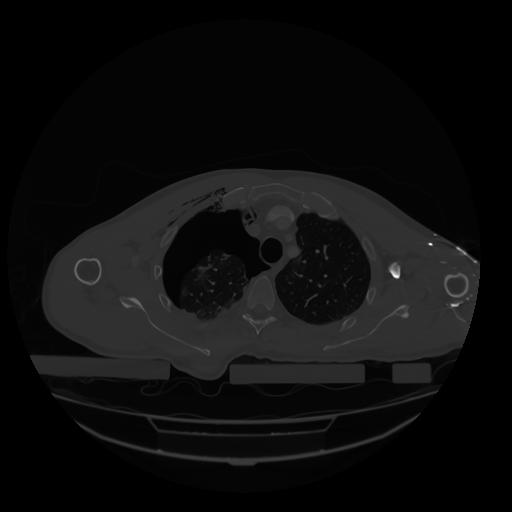

28 CUERPO,CE,Vol,2.0,CUERPO,,